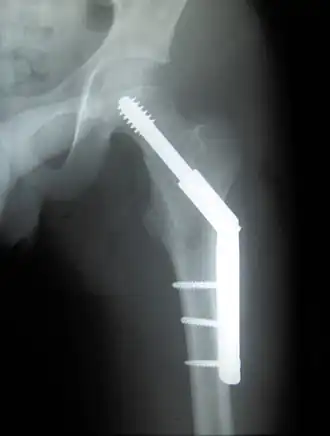

Pertrochantere fractuur

De kans dat een pertrochantere fractuur goed geneest, is groot. Behandeling vindt meestal plaats met een dynamische heupschroef: een lange schroef gaat dwars door de fractuur de heupkop in, en wordt op zijn plaats gehouden met een plaatje dat langs het bot van het dijbeen zit geschroefd met enkele schroeven. Meestal is deze botbreuk binnen de 3 tot 6 maanden genezen. Het is, zeker bij ouderen, niet gebruikelijk de dynamische heupschroef weer te verwijderen; de risico’s van een tweede operatie en eventueel van een nieuwe fractuur zijn groter dan de kans op klachten. Wanneer er sprake is van osteoporose kan de kans op een nieuwe fractuur kleiner gemaakt worden door de osteoporose te behandelen. Bij jonge mensen wordt soms wel overwogen de plaat en de schroeven te verwijderen; bij hen kan het materiaal de spanning op het bot vergroten, waardoor de kans op een nieuwe botbreuk bij een ongeluk juist groter wordt.

Er kunnen allerlei problemen ontstaan met het materiaal: schroeven en plaat kunnen breken, er uitgewerkt worden of aan de andere kant naar buiten komen en in het gewricht steken. Dit kan veroorzaakt worden door verkeerde plaatsing van het materiaal, maar ook door slechte kwaliteit van het bot. Een nieuwe operatie en eventueel vervanging van het heupgewricht door een total-hipprothese kan nodig zijn.